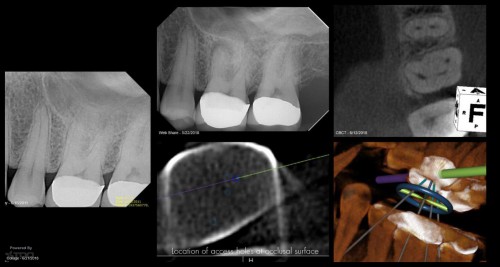

Because this was a Zirconia crown, my approach was to make a “staging platform” where I thought the access points would be. Proabbaly made the platform larger than I needed to. In this case, the X-nav was spot-on. I’m nowhere near Charles or Pushpak, but I am getting more comfortable with it. This took longer than I thought because I had to change the plan when we discoved the angles to get into the MB1 and MB2 required the handpiece to be “too vertical” and the cameras wouldn’t read them. So the angle of the dangle had to be altered during the procedure. Kind of a PIA….. gbc